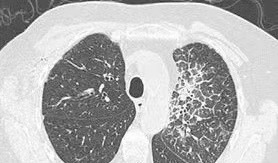

癌性淋巴管炎在影像学上容易与间质性肺炎、间质性肺水肿、放射性肺炎、肺纤维化等疾病混淆。因为癌性淋巴管炎的影像表现为从肺门到肺野呈放射状不均匀阴影,支气管增厚,网状结节,甚至肺实质间质水肿和磨玻璃影。高分辨率CT显示小叶间隔增厚成串珠状,有助于鉴别。这种影像表现可以分布在一个或两个肺上,局部或广泛,对称或不对称。如果发生广泛的癌性淋巴管炎,会影响肺通气功能,患者会出现更多的呼吸困难症状。